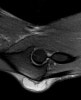

MRI : 주두 점액낭염(Olecranon bursitis)